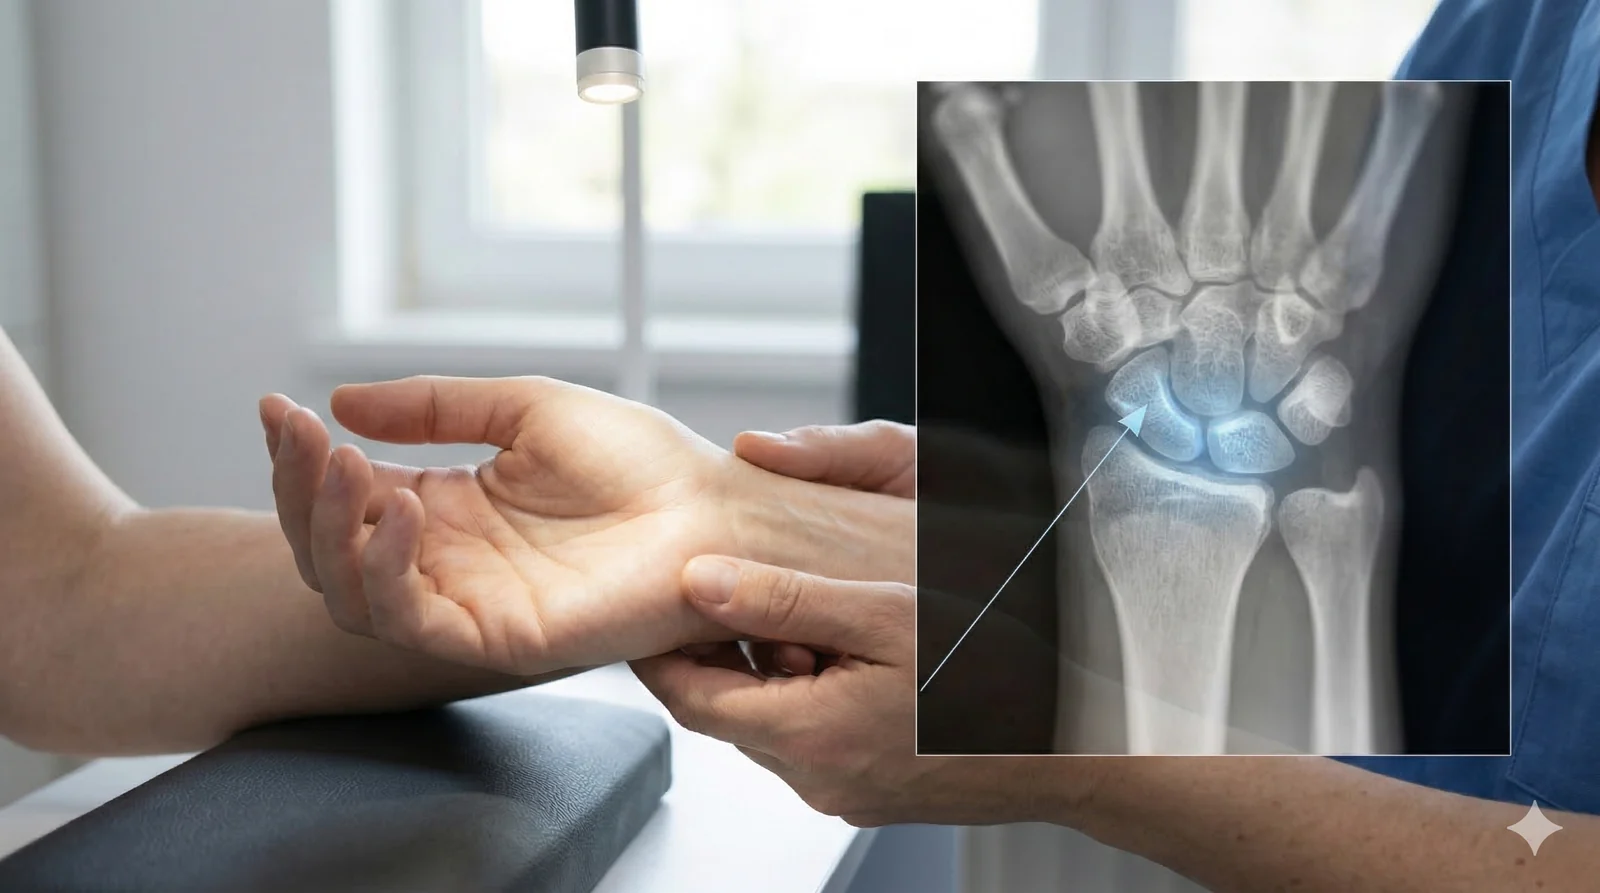

Kość księżycowata jest jedną z ośmiu kości nadgarstka i znajduje się w jego centralnej części. Odgrywa ważną rolę w stabilizacji nadgarstka oraz w przenoszeniu obciążeń pomiędzy kośćmi przedramienia a ręką.

W chorobie Kienböcka dochodzi do zaburzenia dopływu krwi do tej kości. Niedostateczne ukrwienie prowadzi stopniowo do osłabienia jej struktury, zapadania się fragmentów kostnych oraz wtórnych zmian w innych elementach nadgarstka. W bardziej zaawansowanych stadiach może to prowadzić do przewlekłego bólu i trwałego ograniczenia ruchomości ręki.

We wczesnym stadium zmiany w kości księżycowatej mogą nie być widoczne w badaniu RTG. Pierwsze zdjęcie rentgenowskie bywa prawidłowe, mimo że pacjent odczuwa ból.

Najbardziej czułym badaniem pozwalającym wykryć wczesne stadium choroby jest rezonans magnetyczny (MRI), który umożliwia ocenę ukrwienia kości oraz jej struktury wewnętrznej. Dlatego w przypadku utrzymujących się dolegliwości bólowych nadgarstka konieczna bywa dokładniejsza diagnostyka obrazowa.

Stopień zaawansowania choroby Kienböcka ocenia się najczęściej według klasyfikacji Lichtmana. Opisuje ona, jak bardzo zmieniła się struktura kości księżycowatej oraz czy choroba zaczęła wpływać na inne elementy nadgarstka.

**Stadium I** – najwcześniejszy etap choroby. Pacjent odczuwa ból, jednak RTG często nie wykazuje zmian. Dopiero MRI pozwala wykryć zaburzenia ukrwienia kości.

**Stadium II** – kość księżycowata zaczyna ulegać zagęszczeniu w RTG. Jej struktura zmienia się, ale kształt jest jeszcze zachowany.

**Stadium III** – dochodzi do zapadania się kości księżycowatej oraz zaburzenia biomechaniki nadgarstka.

**Stadium IV** – najbardziej zaawansowany etap. Dochodzi do wtórnych zmian zwyrodnieniowych całego nadgarstka.

Wczesne wykrycie choroby – w stadium I lub II – daje zdecydowanie najlepsze rokowanie i największe możliwości terapeutyczne.